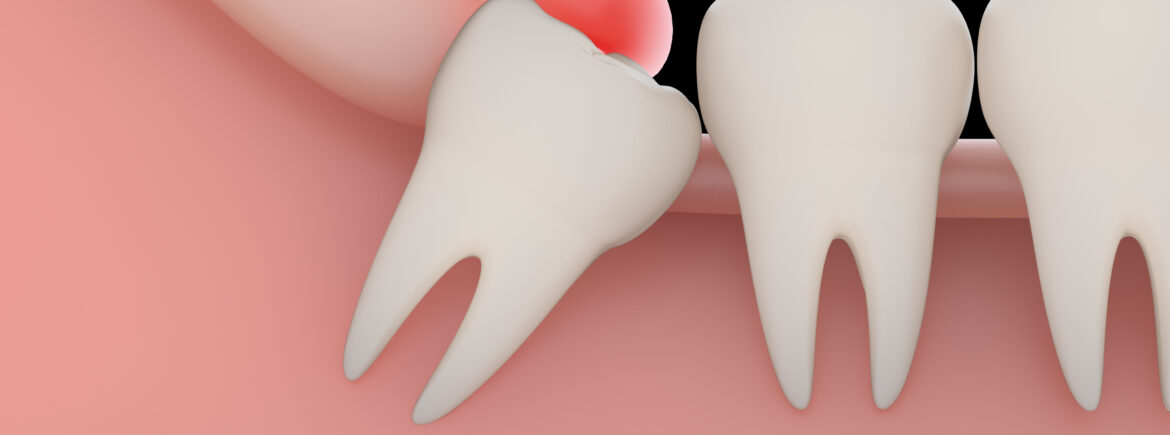

A dor na região posterior da mandíbula, associada à dificuldade de mastigação e limitação de abertura bucal, é um cenário recorrente na rotina clínica. Em muitos